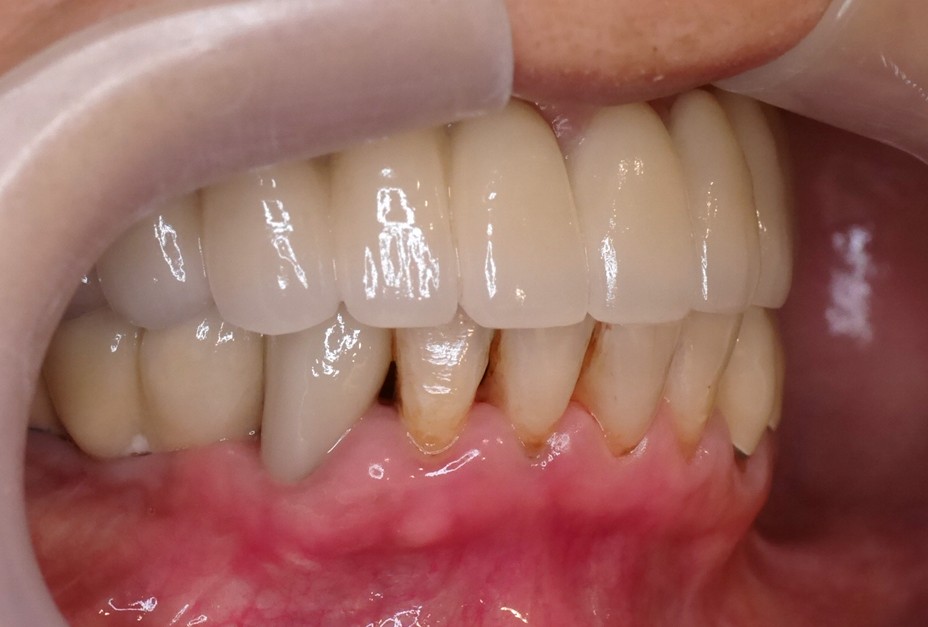

假牙完成